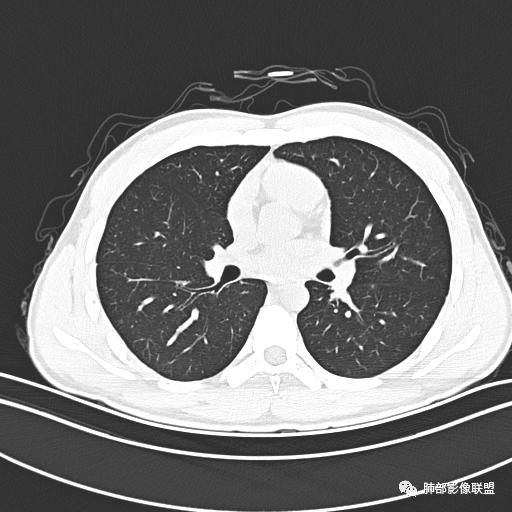

小强:青年,发热,皮疹;双肺散在结节,周围磨玻璃,点晕征,疱疹病毒感染,鉴别荚膜组织胞浆菌,结核。 大雄:青年,急性起病,发热伴全身皮疹2天,抗病毒治疗体温有下降。双肺随机分布大小不等类圆结节,“点晕征”。考虑水痘-疱疹病毒(VZV)血播询问接触史,查体皮疹分布以及形态基本可诊断。 王开金江津中心医院呼吸科:青年男性,起病急,病程短,以发热,皮疹为首发症状,感染指标以单核细胞升高为主,胸部ct双肺多发结界,周围有晕,点晕表现,随机分布,同意於老师意见,水痘疱疹病毒血流感染累及肺。 王秀仙:双肺多发大小不等结节,周围有晕,边缘模糊,呈点晕征表现。青年,急性起病,发热伴全身皮疹2天,抗病毒治疗体温有下降。考虑疱疹病毒。鉴别荚膜组织胞浆菌。 傅昌瑜:19岁男性,发热、全身皮疹2天,单核细胞增高,双肺多发结节,结节边缘见边界不清磨玻璃影。点晕征+发热、全身皮疹+单核细胞增高——考虑水痘-带状疱疹病毒肺炎。 一切∮随缘:年轻男性,发热,皮疹两天,实验室,CRP,PCT增高,影像:双肺多发散在磨玻璃结节,边界欠清,大小不等,呈点晕征改变,以血管束周围分布为主,局部血管束略增粗,其它无明显改变,考虑:1:病毒性肺炎(水痘疱疹病毒?不知道皮肤有无改变)2:真菌(组织胞浆菌,血管侵袭性肺曲霉)3:GPA4:寄生虫(实验室没有看到嗜酸细胞增高) 赵山河:双肺散在结节,周围有晕,边缘模糊,呈点晕征表现。青年,急性起病,发热伴全身皮疹2天,抗病毒治疗体温有下降。考虑水痘—疱疹病毒感染。洪桥爱:青年男性,发热、皮疹2天,伴瘙痒,皮疹于面部首发,之后进展至全身,虽然没有对皮疹进行描述,但是从出疹时间及皮疹进展情况,伴瘙痒,应该就是个水痘患者;CT提示双肺随机分布结节影,部分结节伴有边界不清晕征,考虑水痘血播肺。 刘强:年轻男性,急性起病,皮疹,发热,抗感染治疗体温下降,说明有效。影像表现为散在点晕征,感染类疾病谱(疱疹病毒,真菌,结核),结合年龄,皮肤皮疹,考虑水痘-疱疹病毒性肺炎。 小兜:男性,19岁,发热皮疹两天,颜面部至全身,CRP,降钙素及单核增高。CT示双肺散在小结节,周围伴磨玻璃影,点晕征,考虑为水痘-带状疱疹病毒(varicella-zoster virus,VZV)肺炎 必有路:青年,皮疹+发热+“点晕征”→水痘-疱疹病毒(VZV) 许慧良:青年男性患者,发热、皮疹2天,体温最高38.5℃,第3天皮疹扩展至全身,伴瘙痒,胸部CT:双肺多发随机分布的小结节,结节周边见边界模糊的晕征,考虑水痘病毒感染流心明智:男,19,急性起病,发热伴全身皮疹2天。出疹顺序头→全身,抗病毒有效。胸部CT:两肺多发大小不等类圆形实性小结节影,随机分布,结节周围环绕GGO,边界模糊,呈点晕征。出疹特点是关键,未提示。考虑:血播病毒性肺炎,水痘-疱疹病毒?麻疹?鉴别荚膜组织胞浆菌、TB、血管炎、寄生虫等。 浪迹天涯:病灶多为5-10mm大小结节,结节周围可见磨玻璃样的晕环,常多发,可分布于肺内任何区域,考虑水痘—带状疱疹病肺炎如果短时间内有新的一个区域浸润,更加能说明,